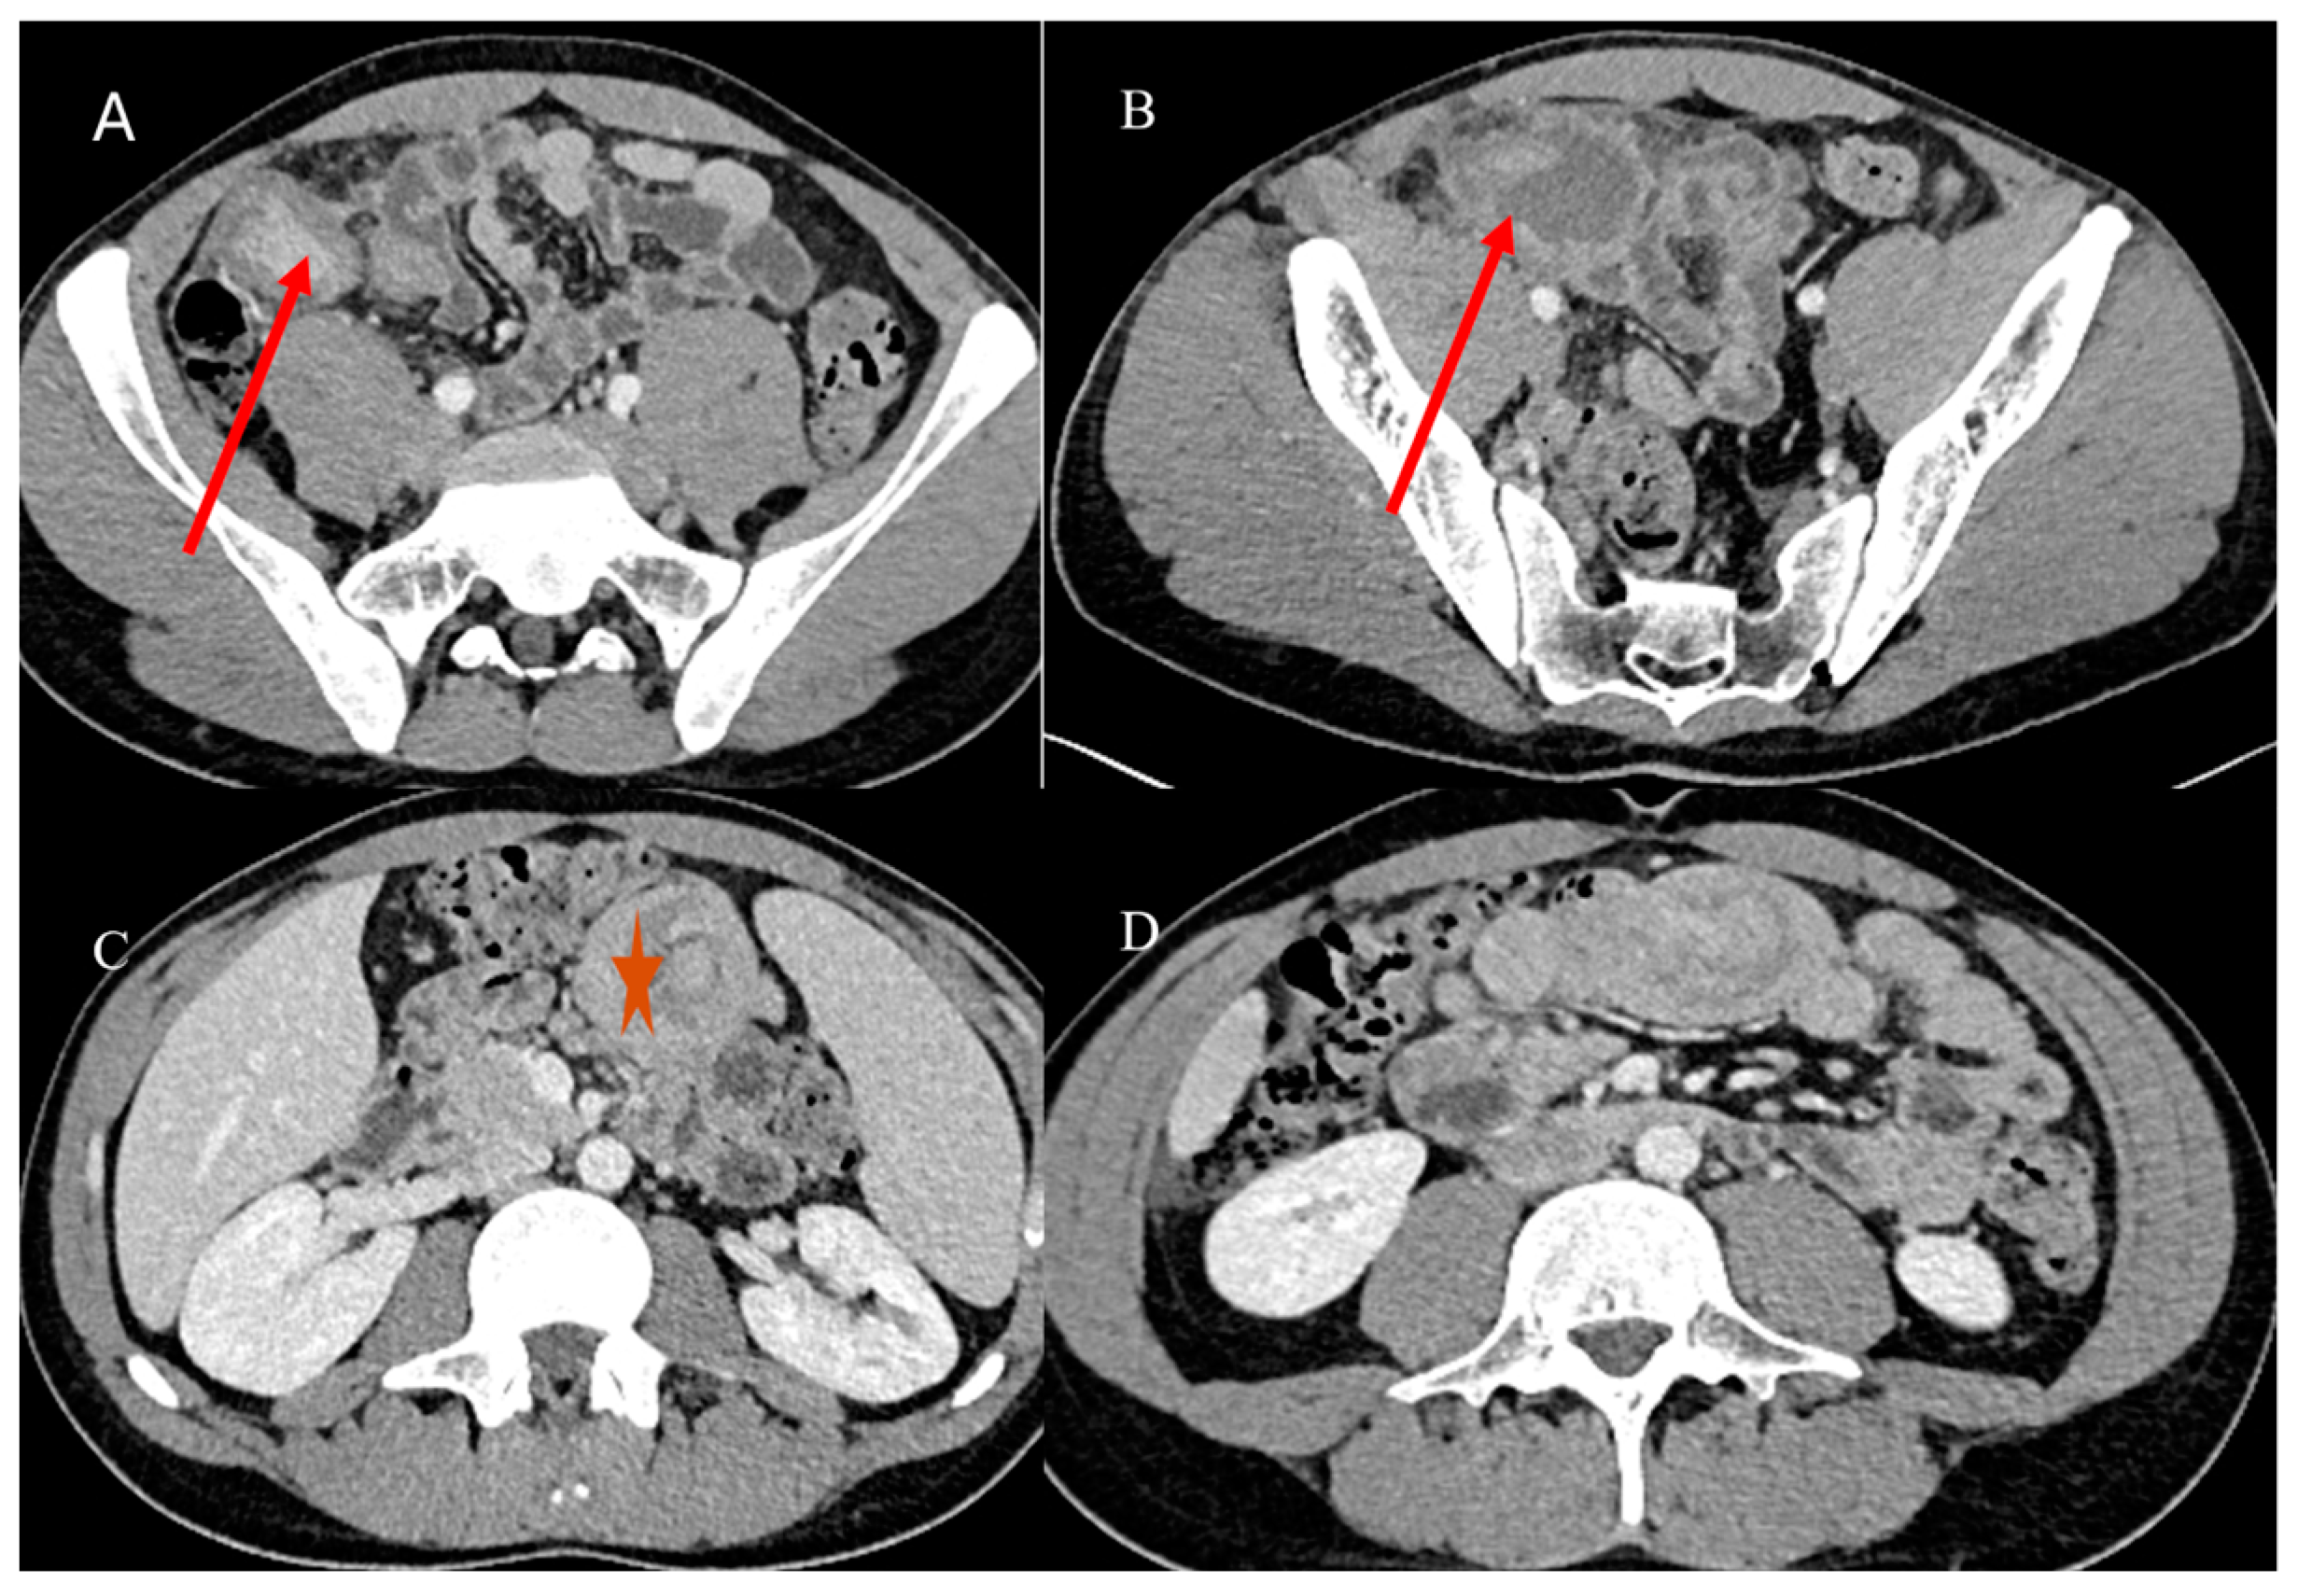

- Marsicovetere, P.; Ivatury, S.J.; White, B.; Holubar, S.D. Intestinal intussusception: Etiology, diagnosis, and treatment. Clin. Colon. Rectal Surg. 2017, 30, 30–39. [Google Scholar] [CrossRef] [PubMed]

- Kim, Y.H.; Blake, M.A.; Harisinghani, M.G.; Archer-Arroyo, K.; Hahn, P.F.; Pitman, M.B.; Mueller, P.R. Adult intestinal intussusception: CT appearances and identification of a causative lead point. Radiographics 2006, 26, 733–744. [Google Scholar] [CrossRef]

- Choi, S.H.; Han, J.K.; Kim, S.H.; Lee, J.M.; Lee, K.H. Intussusception in adults: From stomach to rectum. AJR Am. J. Roentgenol. 2004, 183, 691–698. [Google Scholar] [CrossRef]

- Panzera, F.; Di Venere, B.; Rizzi, M.; Biscaglia, A.; Praticò, C.A.; Nasti, G.; Mardighian, A.; Nunes, T.F.; Inchingolo, R. Bowel intussusception in adult: Prevalence, diagnostic tools and therapy. World J. Methodol. 2021, 11, 81. [Google Scholar] [CrossRef] [PubMed]

- Honjo, H.; Mike, M.; Kusanagi, H.; Kano, N. Adult intussusception: A retrospective review. World J. Surg. 2015, 39, 134–138. [Google Scholar] [CrossRef] [PubMed]

- Wang, N.; Cui, X.Y.; Liu, Y.; Long, J.; Xu, Y.H.; Guo, R.X.; Guo, K.J. Adult intussusception: A retrospective review of 41 cases. World J. Gastroenterol. World J. Gastroenterol. 2009, 15, 3303. [Google Scholar] [CrossRef]